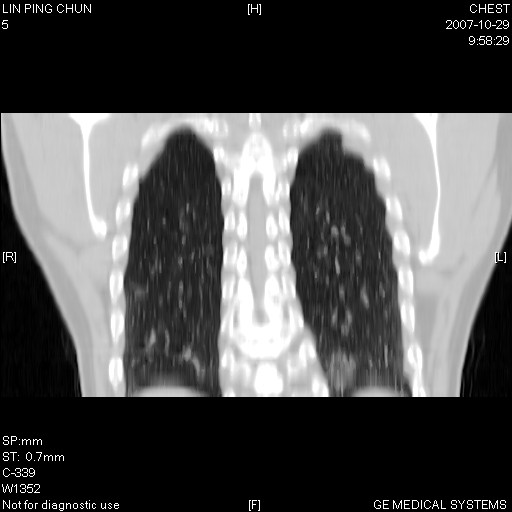

标题: CT10239:男,42Y.我自己的胸部CT扫描,今天10点突然咯血一次。 [打印本页]

标题: CT10239:男,42Y.我自己的胸部CT扫描,今天10点突然咯血一次。

我自己胸部ct扫描,求助大家,我自己还不能给自己诊断。其他层面纵隔窗无异常。

补充:男,42y.今天10点突然咯血一次。余无异常。

左肺下叶后基底段小片结节状影,内部似见同心圆状分布条絮状影,整个病灶,质不实.局部见增粗血管影.

考虑;球形肺炎可能大.自已的身体如此重要,不进一步局部薄层及hrct?

左下肺后基底段磨玻璃样影,很多病都可以。不能吊以轻心。应该做局部增强hrct进一步检查,并严格抗炎治疗后复查或经皮活检。

左下肺后基底段小斑片泪膜玻璃样影,其内可见空泡影,边缘可见小毛刺影。建议抗炎治疗复查,肿瘤待排